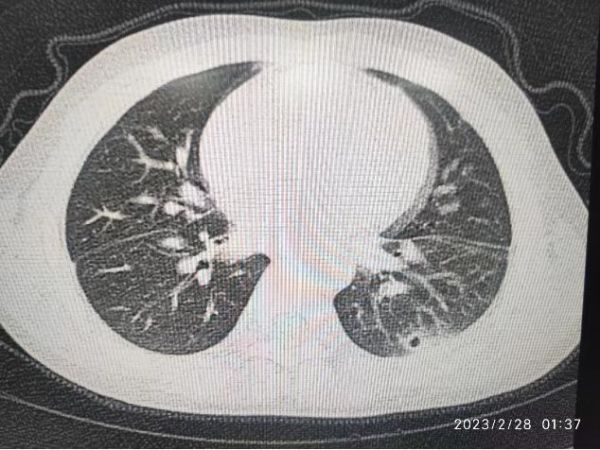

奇奇起初因为“头痛、呕吐、间断发热6天”到儿科住院治疗,经过检查被诊断为“化脓性脑膜炎”,经过有效治疗后,病情逐渐好转的奇奇却再次发热,经过再三仔细询问了解到,奇奇平时经常发热,喜欢喝生水,生吃螃蟹,饮食不太注意卫生,经多次血常规检查,发现他的嗜酸粒细胞升高,医生高度怀疑寄生虫感染,于是完善了寄生虫抗体检验,果然提示肺吸虫“阳性”,肺部CT也显示他的左肺下叶部分病灶内有空洞。